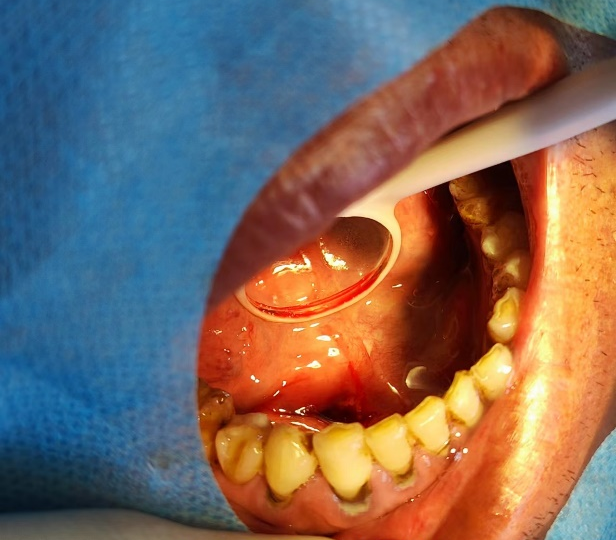

患者手术过程拍摄照片

做好术前准备后,薛主任在门诊手术室,局部浸润麻醉下进行下颌下腺导管内结石取出手术。手术过程中,手术创口较小,创口出血较少,患者配合程度较高,手术用时较短,薛主任以最优的手术方案成功取出患者口内下颌下腺导管口内长约18mm、宽约16mm巨大结石。为患者提供了对身体损伤最小,创口最优,花钱最少的处理方案,以最快的时间解决了患者的病痛。